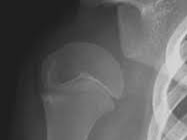

어깨 관절은 팔뼈(상완골), 견갑골, 쇄골 등 세 가지 주요 뼈와 이를 연결하는 근육, 힘줄, 인대 등으로 구성되어 있습니다. 특히 ‘회전근개(rotator cuff)’라고 불리는 네 개의 근육은 어깨의 회전과 안정성 유지에 중요한 역할을 합니다. 문제는 이 구조가 매우 유연하면서도 섬세하다는 점입니다. 작은 외상이나 반복적인 사용만으로도 손상이 일어나기 쉽습니다.